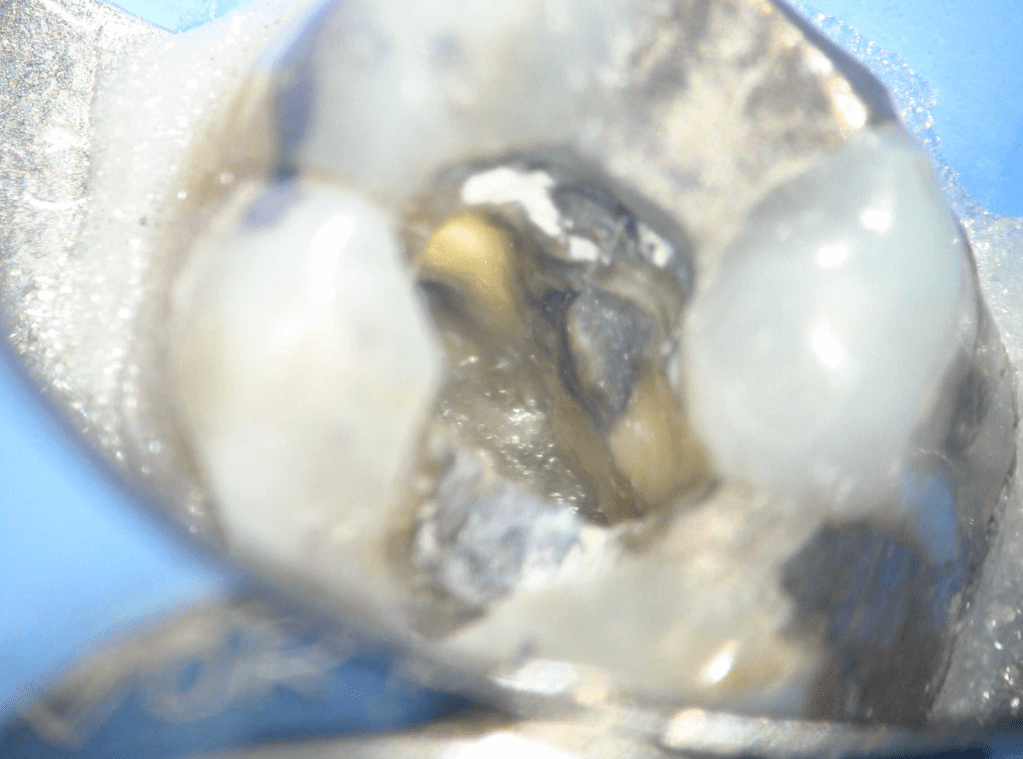

Fisura, remoción amalgama para explorar